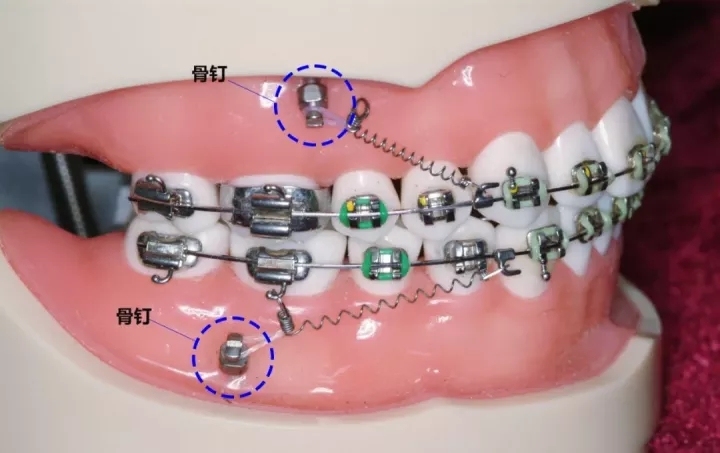

迷你骨钉简称骨钉,又叫支抗钉、种植钉,学名“种植支抗”或“暂时性支抗装置”,由纯钛或不锈钢制作,是植入牙槽骨的临时性迷你小钉子,矫正结束后就会移除的,而骨钉缺口会自行复原长好。

骨钉的功能是提供施力的固定源,帮助拉动牙齿,24小时施力,可以达到传统矫正很难做到的效果,能够快速改正龅牙脸型,真正做到该动的牙动,不该动的牙不动,提高矫正效果和时间。

骨钉是什么样子的?

它长得和普通的钉子很像,但体积很小,一般长度6mm~12mm不等,直径1.5mm左右。不同大小的钉子所用于植入的位置不一样,一般后牙区用长一些的,前牙区用短一点儿的,因为牙槽骨的厚度不一样。